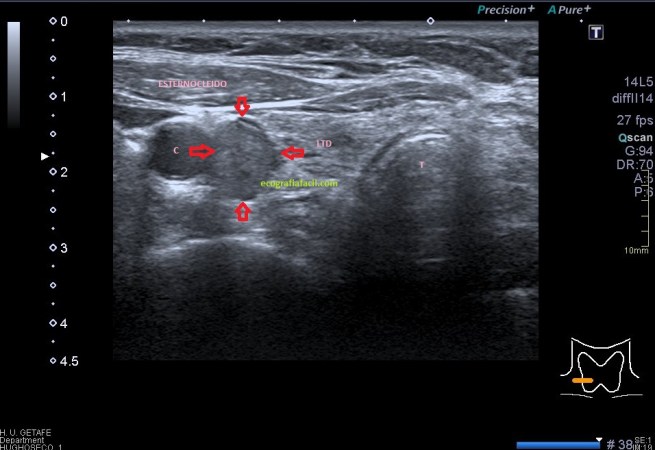

Criptorquidia: El testículo no descendido es una de las anomalías genitourinarias más comunes en niños. La mayoría de los testículos no descendidos son palpables y se localizan en el canal inguinal. Su aspecto ecogénico es normal, salvo si son vistos en la edad adulta, que pueden ser más pequeños y de ecogenicidad alterada. Objetivamente no van a estar en las bolsas y los vamos a encontrar donde marca el picto de la imagen 12. En ocasiones necesitan tratamiento quirúrgico. La flecha amarilla fina y alargada te marca la profundidad anómala debido a la piel y el tejido celular subcutáneo típico de la región inguinal, observa como cambia esta imagen respecto de cualquiera de las anteriores con los testes en sus bolsas.